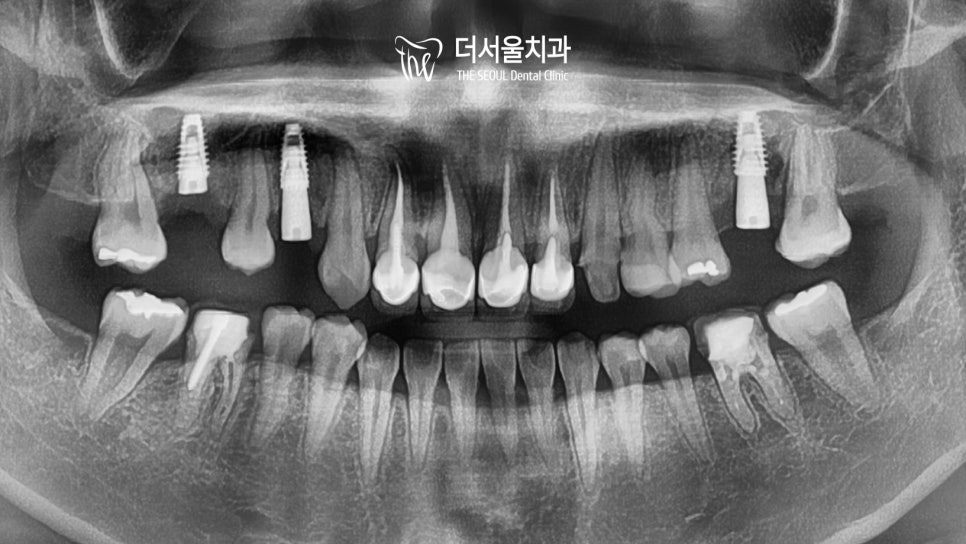

인비절라인을 통해 치열 정돈을 마친 후

본격적인 임플란트 식립을 준비했습니다.

컴퓨터 분석을 사용하여

주변 조직과의 위치, 인접치, 대합치 등을 확인하고

계산된 위치에 식립을 도와드렸는데요.

이때 정말 신중하고 꼼꼼한 과정을 필요로 합니다

한번 심어진 것은 재수술을 통해 빼내지 않는 이상

이동이 불가하기 때문에 계산을 잘해야 되죠.